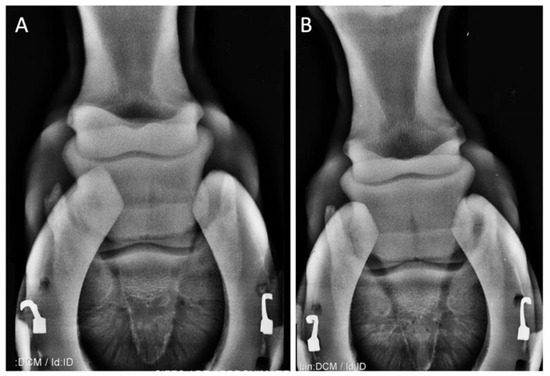

| (3) 14-year-old Holst. mare jumping horse | Distal intertarsal joint arthritis | Lameness Flexion test | 2 3 | 1 2 | 0 1 | 0 0 | 0 0 |

| (4) 15-year-old NRPS mare jumping horse | Distal intertarsal joint arthritis | Lameness Flexion test | 3 3 | 2 2 | 1 1 | 0 1 | 0 0 |